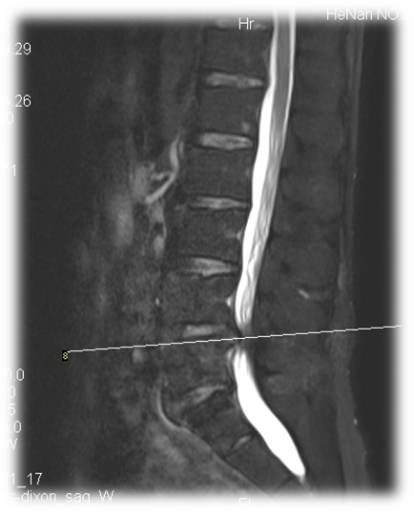

术前 图片1